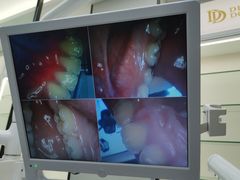

• 牙博士口腔(杨浦店)

• -牙博士口腔(杨浦店)